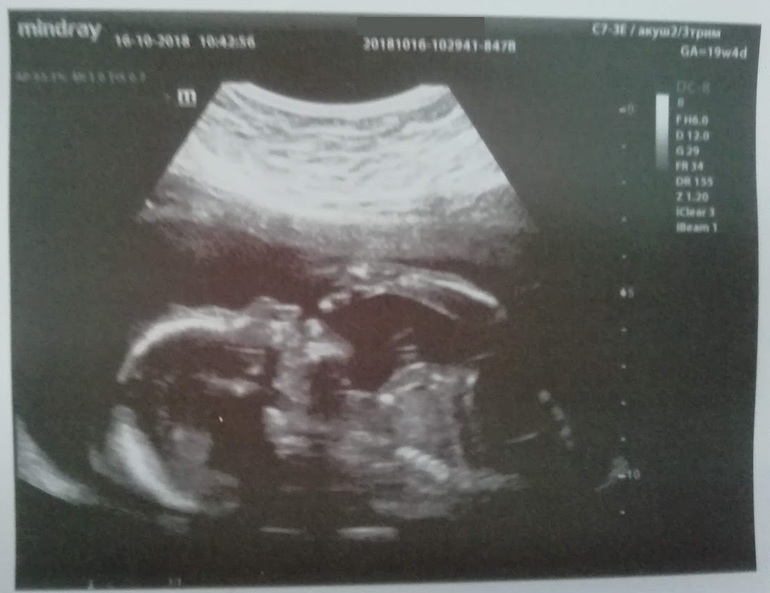

Но сегодня снова настрой позитивный :))) Мы ждем девочку!! Развивается по сроку М, отставания/опережения нет, весит 296 грамм, сидит на попе (в тазовом) и пихает меня ногами в шейку/таз.

Красотка показала уже одно из главных умений: сосет большой палец.